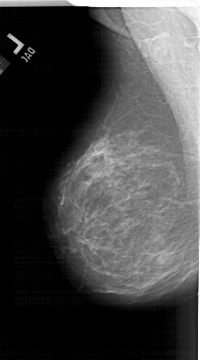

A_1515_1.LEFT_CC

LEFT_CC LINES 6541 PIXELS_PER_LINE 3811 BITS_PER_PIXEL 12 RESOLUTION 43.5 NON_OVERLAY